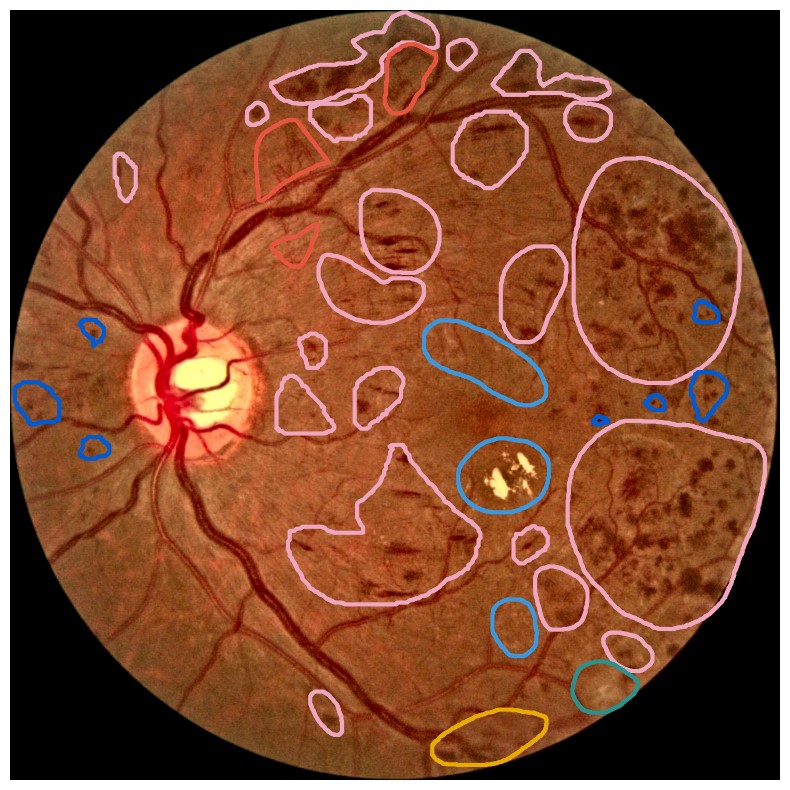

Diabetes is a disease with increasing prevalence, and diabetic retinopathy (DR) is one of the most common complications (World Health Organization, 2022). \AcDR is characterized by retinal abnormalities, which damage the eye and can lead to blindness. Its severity depends on the type and amount of retinal abnormalities: \AcHE, microaneurysms (MA), hard exudates (EX), soft exudates (SE), intraretinal microvascular abnormalities (IRMA), and neovascularization (NV). \AcDR is graded from 00 to 4444 (no DR, mild, moderate, and severe nonproliferative DR, and proliferative DR), as described by Wilkinson et al. (2003). DR grading of fundus images is traditionally a manual process requiring medical expertise. Figure 1 provides examples of fundus images of eyes with increasing severity of DR including the ground truth segmentations of the six retinal abnormalities. These images underline the challenge of identifying relevant medical abnormalities without specialist training.

Figure 1: Example fundus images representing increasing DR severity with segmentation masks of retinal lesions. Level 4 is the most severe type of DR and is associated with a high risk of blindness. Images from the FGADR dataset (Zhou et al., 2021). Dark blue = microaneurysms, pink = hemorrhages, light blue = hard exudates, green = soft exudates, yellow = intra-retinal microvascular abnormalities, and red = neovascularization. Best viewed with zoom.

Concept explanation methods are attractive for medical applications because they measure how much the deep neural networks are influenced by high-level concepts representing clinical findings (Salahuddin et al., 2022). A concept can be described as a theme or topic, e.g., ’stripes’ and ’dots’ for natural images, or diagnostic findings such as ’hemorrhages’ and ’microaneurysms’ for fundus images. The six different diagnostic concepts used for this work is shown with the ground truth segmentation masks in Figure 1. \AcTCAV (Kim et al., 2018) and Concept Bottleneck Models (Koh et al., 2020) are two concept-based methods that have several advantages above heatmap methods. Both allow the user to define the concepts, which ensures relevant and meaningful concepts that are interpretable for the end-users. How the concepts are used varies between the two explanation methods and is outlined in Sections 2.1 and 2.2. Moreover, the relative importance of the concepts can be quantitatively measured. For Testing with Concept Activation Vectors (TCAV), concept scores can be generated for a group of images, e.g. images belonging to the same class, allowing the user to investigate whether the model has learnt aspects coherent to domain knowledge and diagnostic guidelines. CBMs, on the other hand, allow the user to directly modify the model’s intermediate concept predictions at test time and observe how this affects the final model prediction. This way of manipulating the model after training is attractive in the medical field, e.g. if the clinician wants to increase the emphasis of a concept in the image that the model missed. While TCAV explains models post-hoc, i.e., predicting the concepts after the classification model has been trained, CBMs provide ad-hoc explanations, where the prediction of the concepts are trained together with the classification model. Even though concept explanations can be more intuitive than heatmaps for medical doctors, neither TCAV or CBMs have been extensively studied in the field of DR grading. In this work, we thus investigate and compare TCAV and CBMs for explaining deep neural networks trained to grade DR in fundus images.